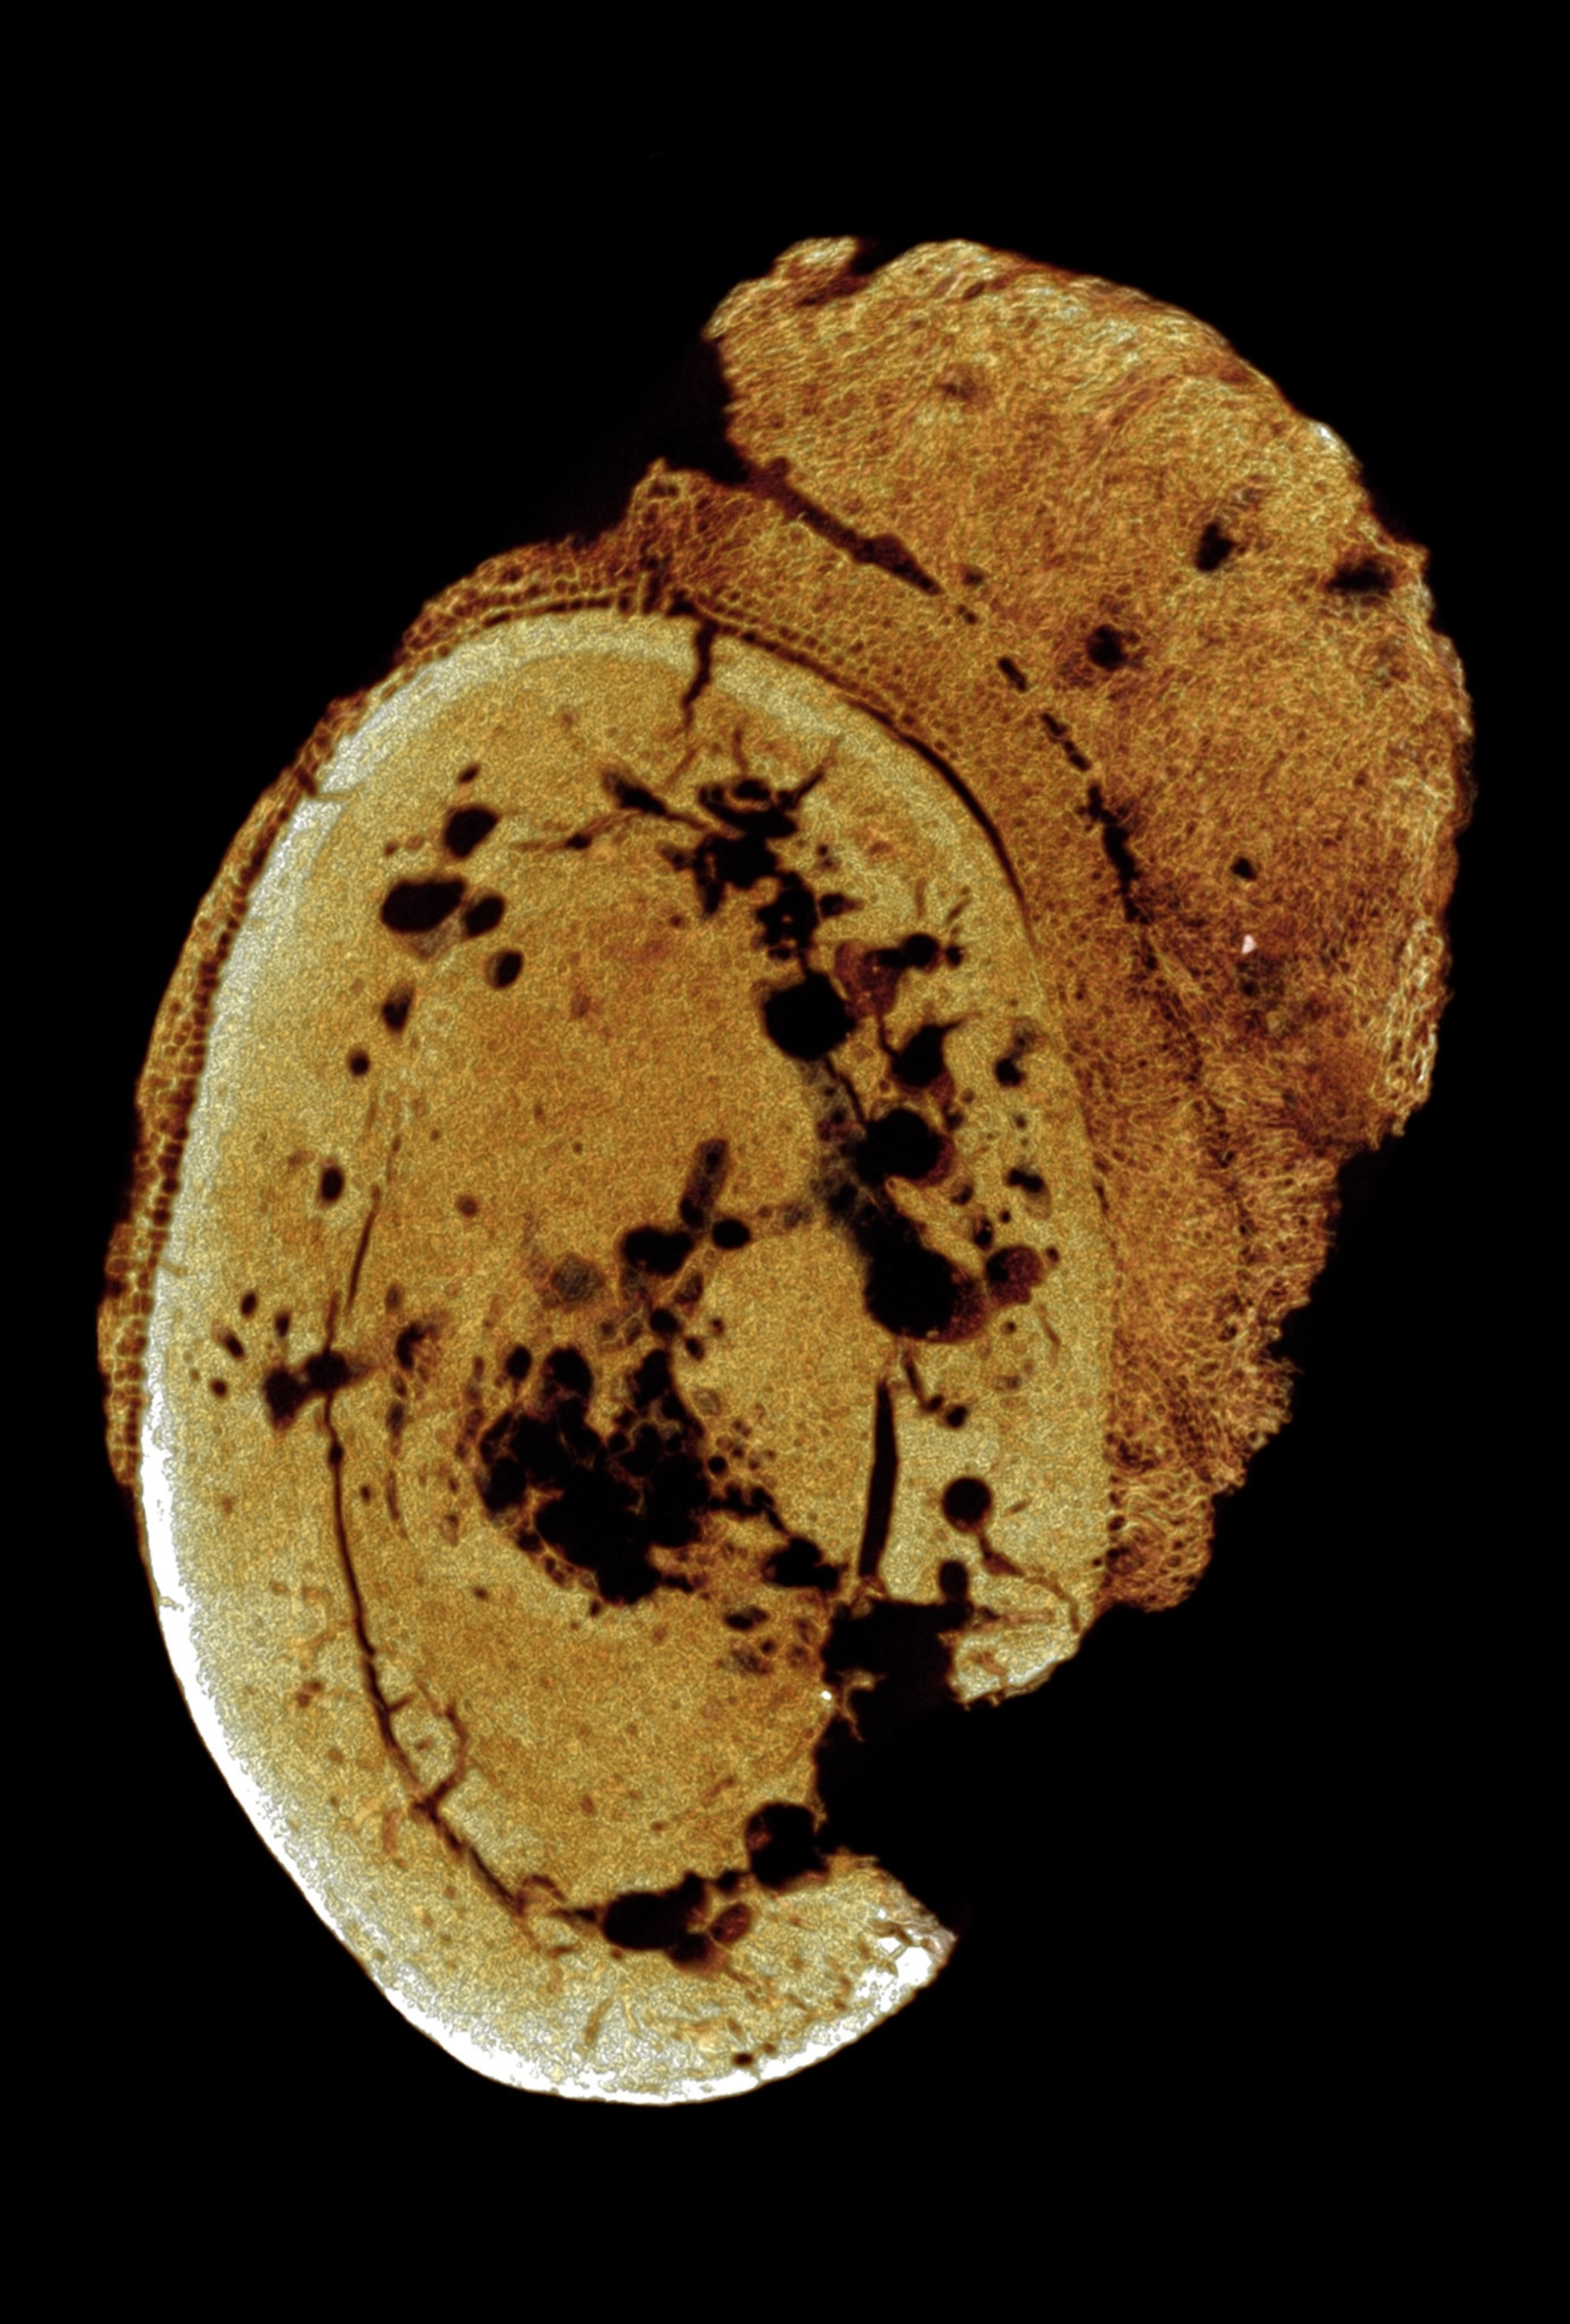

Using 3-D imaging, the researchers have diagnosed an aggressive type of cancer called osteosarcoma in a foot bone belonging to a human relative who died in Swartkrans Cave between 1.6 and 1.8 million years ago.

Using a method called micro-CT imaging, the research team studied detailed 2-D and 3-D images of the fossil’s interior. Images recorded the density differences within the bone and generated views of the fragment from all directions.

The abnormal growth pattern of bone tissue—including a distinctive, cauliflower-like external appearance—led the team to diagnose the condition as osteosarcoma, which today afflicts mostly children and young adults.

“We compared the images,” says Odes, referring to the fossil and a modern biopsy specimen. “It was bingo.”

The fossil, a fragment of a toe bone from the left foot, is the only part of the skeleton that was found. It preserved too little information to determine which hominin species it belonged to, whether it was an adult or a child, or even if the cancer was the ultimate cause of death.